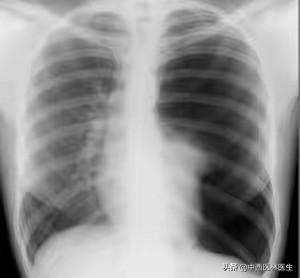

- 肺炎乾いた咳も出るが、息切れなどを伴って長引く傾向がある(下図)。

2.心血管疾患による乾性咳嗽:咳は循環器疾患の典型的な症状ではないが、冒頭で紹介した肺塞栓症の同級生のように、呼吸困難や胸痛、あるいは喀血を伴って空咳の症状を呈する疾患もしばしばあり、診断のためには画像診断だけでなく、臨床検査も必要となる。